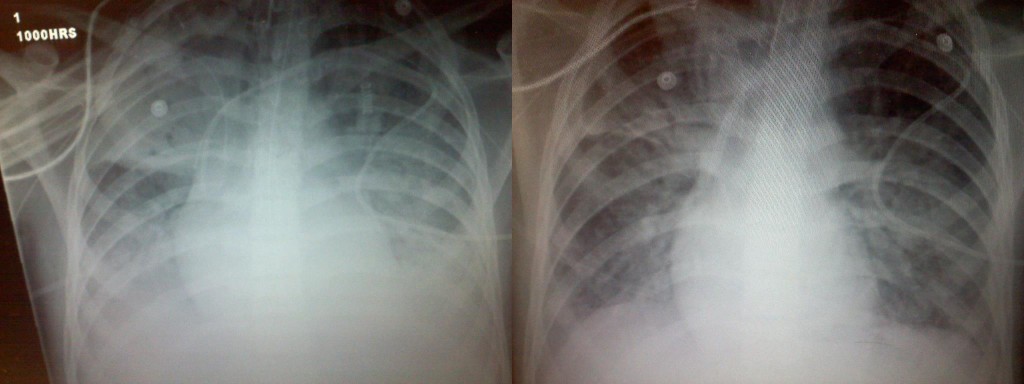

Time passed, and the joy on everyone’s heart was overwhelming. The attending PICU doctor asked if it was okay to get a chest xray of Tyler’s lungs now. She asked for our consent because we still weren’t exactly sure how stable Tyler was at this time, and the movement of getting an xray could destabilize him. Nonetheless, we agreed. When the xray came back, the PICU attending threw her arms in the air and said, “There it is!” Again we were all astonished at what we were looking at; two very different xrays taken only 5 hours apart. Look at the before and after photo and see for yourself. The doctors assured us that there was no way any intervention they provided could have produced the same results.

Mom:

The doctor was too curious about what had happened in Tyler’s lungs to wait for the 6AM xray, and ordered a stat xray. She was astounded and grinning as she showed us the before and after xrays – Tyler’s lungs look better than they have in weeks! In fact, the lower lobes of his lungs haven’t looked this good since his lungs first got in trouble.

I got home around 2AM and just before I went to bed, my cell phone rang! It was Ron McGinn. This time his voice was filled with true joy and excitement. He said a new x-ray showed that Tyler’s lungs were the best they had been in over 4 weeks. The rest of the story is still being written. Tyler still has a long ways to go. But I am confident in the ONE who has done amazing things so far! God is able to do exceedingly more than I could ever dream or imagine! God is able! All for His Glory! Keep praying and keep believing!